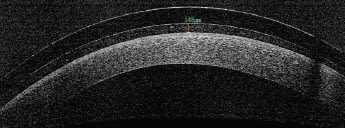

The first consideration is the design itself. Most large-diameter lenses are sclerals. This means that they are designed to vault the entire corneal surface, including the limbal area, and to land on the conjunctiva. A small number of other products are called corneo-scleral lenses, and are fitted to be supported partly by the cornea. Clinical experience suggests that this may not be appropriate for most patients, and in some cases (with keratoconus in particular), this corneal touch could generate a high level of mechanical stress on a limited area of the cornea, triggering a higher risk of scarring (Figure 3). This is why most experts in the field dislike and do not fit corneo-scleral lenses on fragile corneas, especially those subject to scarring (Caroline et al, 2013).

Figure 3. Corneal scarring visible under a corneo-scleral lens fitted on a keratoconus patient.